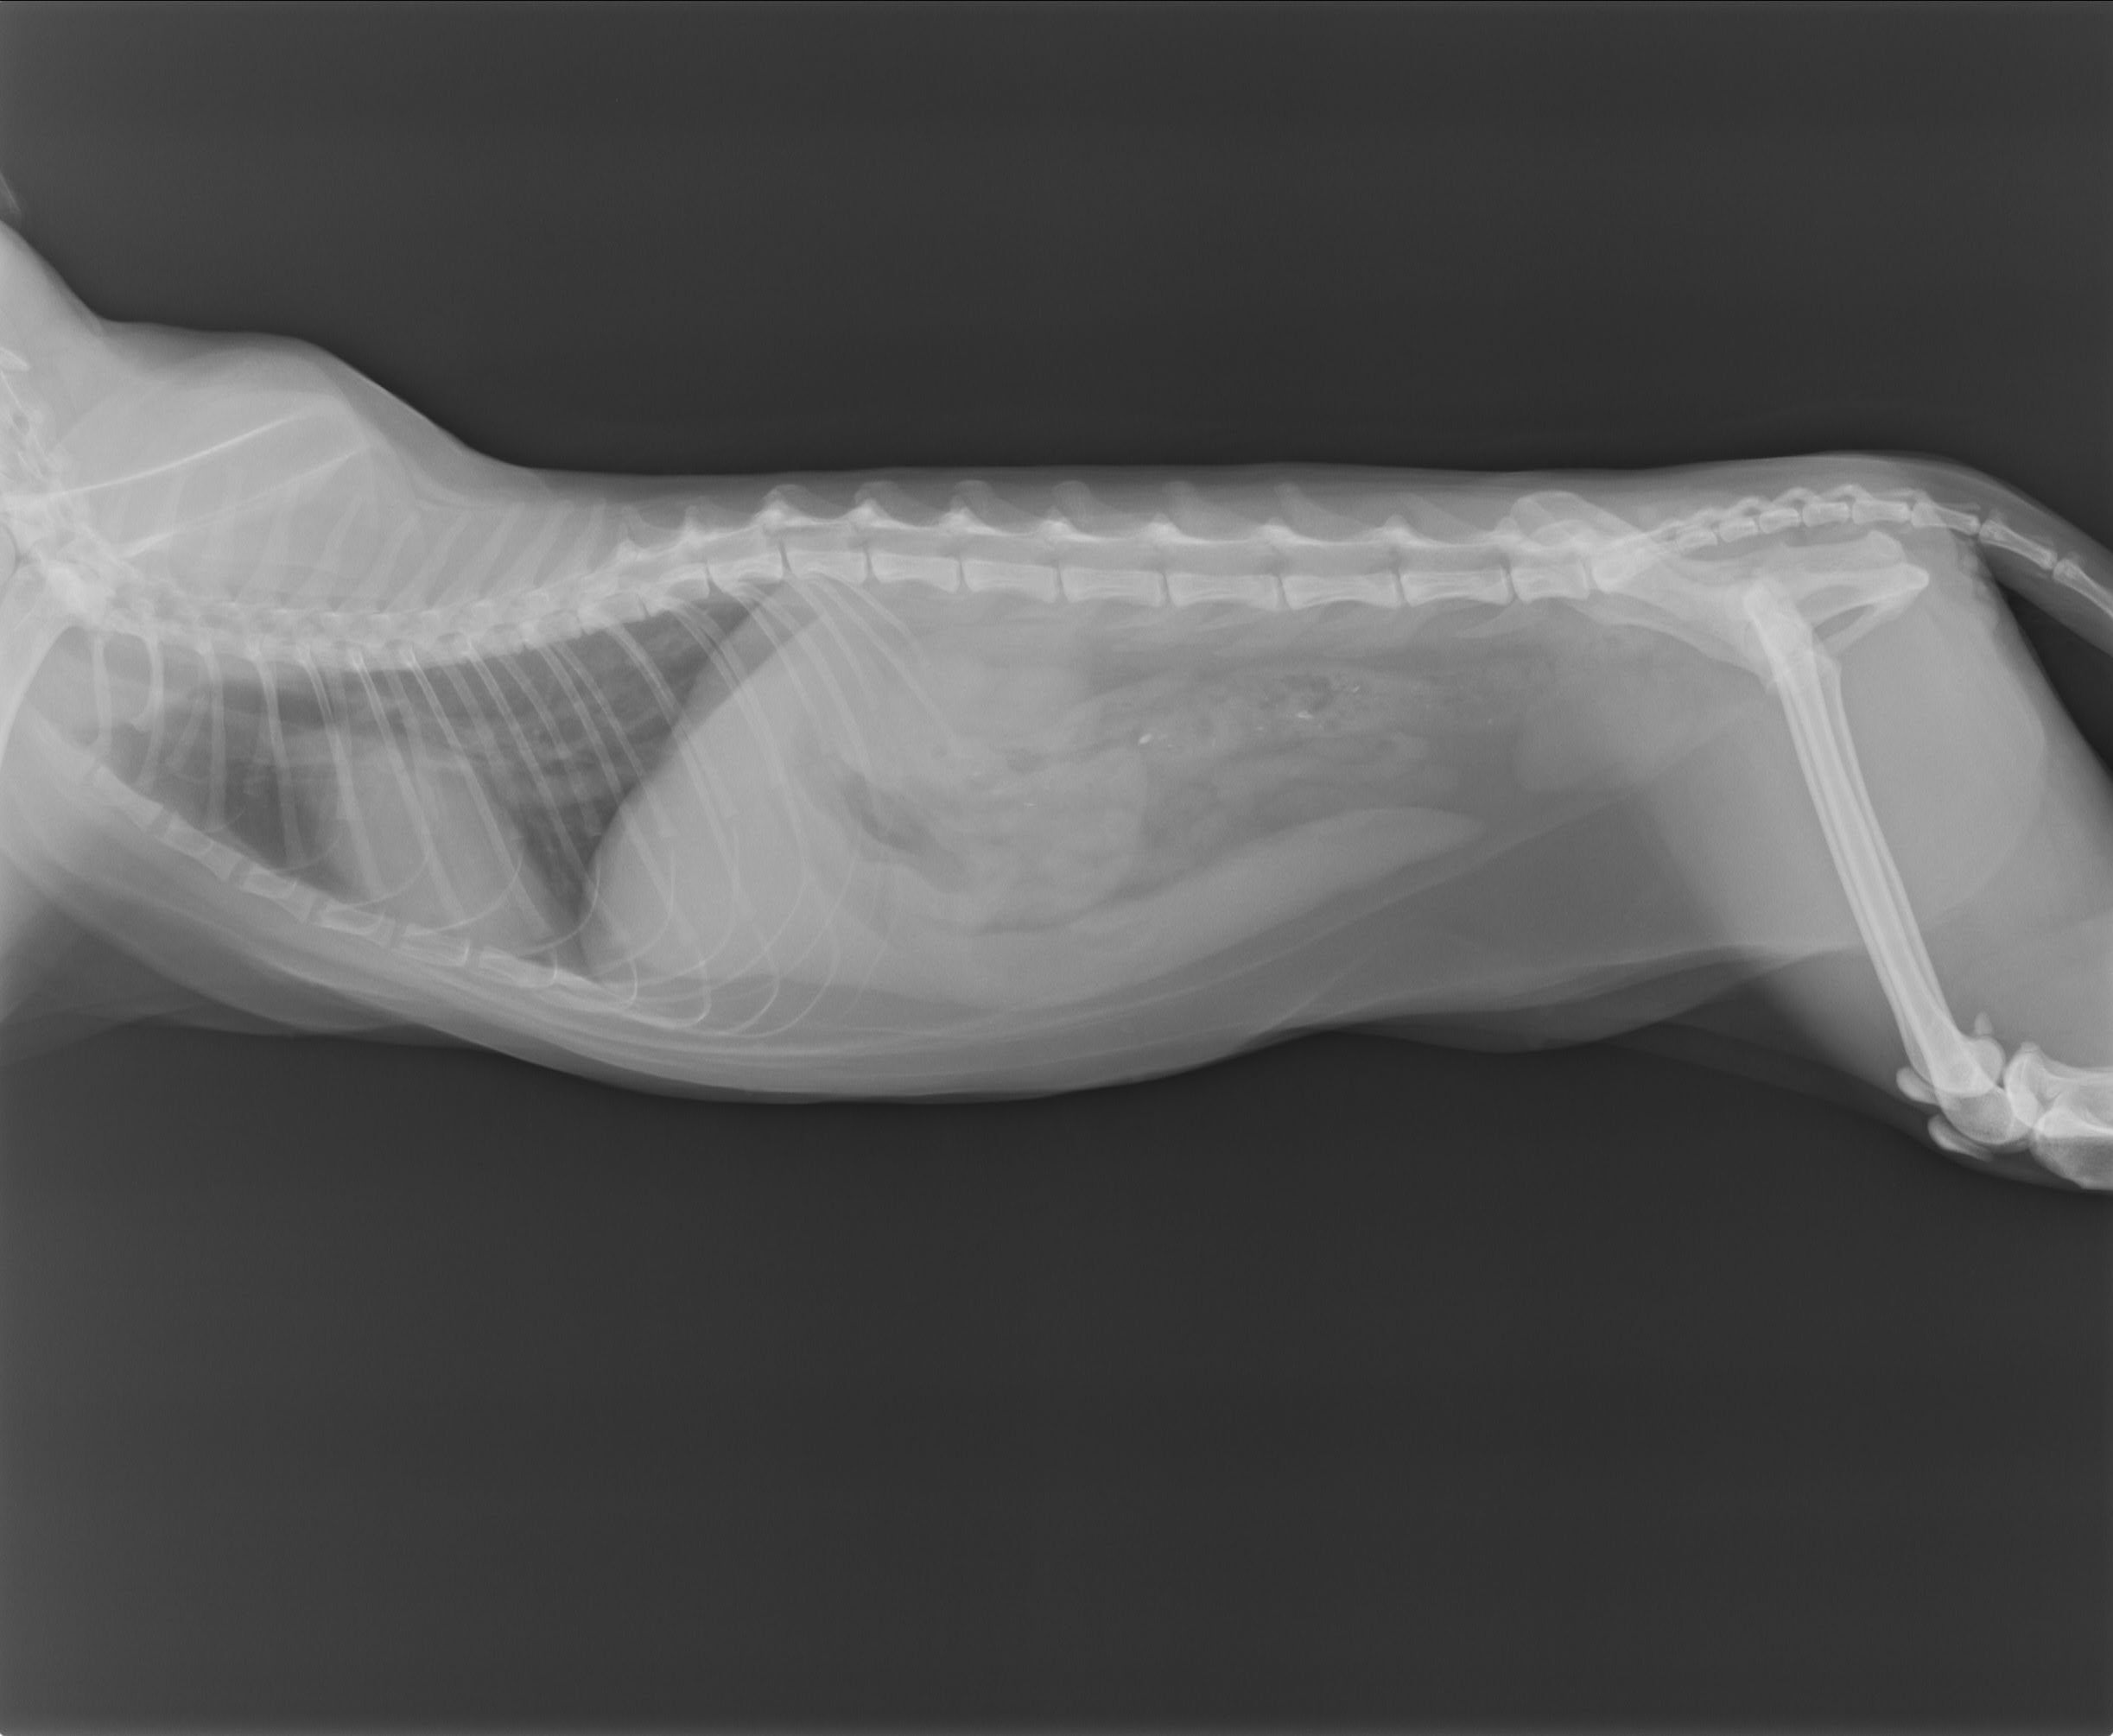

咪咪厭食超過一週,發燒41.3度,有黃疸及黏膜蒼白;血檢發現有嚴重的貧血,肝指數偏高,球蛋白偏高,懷疑有血液寄生蟲,需要另送PCR篩檢;x光發現脾臟腫大,貓二合一篩檢發現有白血病,目前先點滴輸液治療,給予血液寄生蟲藥物及肝藥。動物近況說明: 咪咪目前已於1/12出院。

雖然PCR篩檢結果顯示咪咪沒有血液寄生蟲的,但咪咪還是有貧血、肝指數偏高以及脾臟腫大的問題,所以還是開立1週份的口服藥,之後仍需回診追蹤病況。